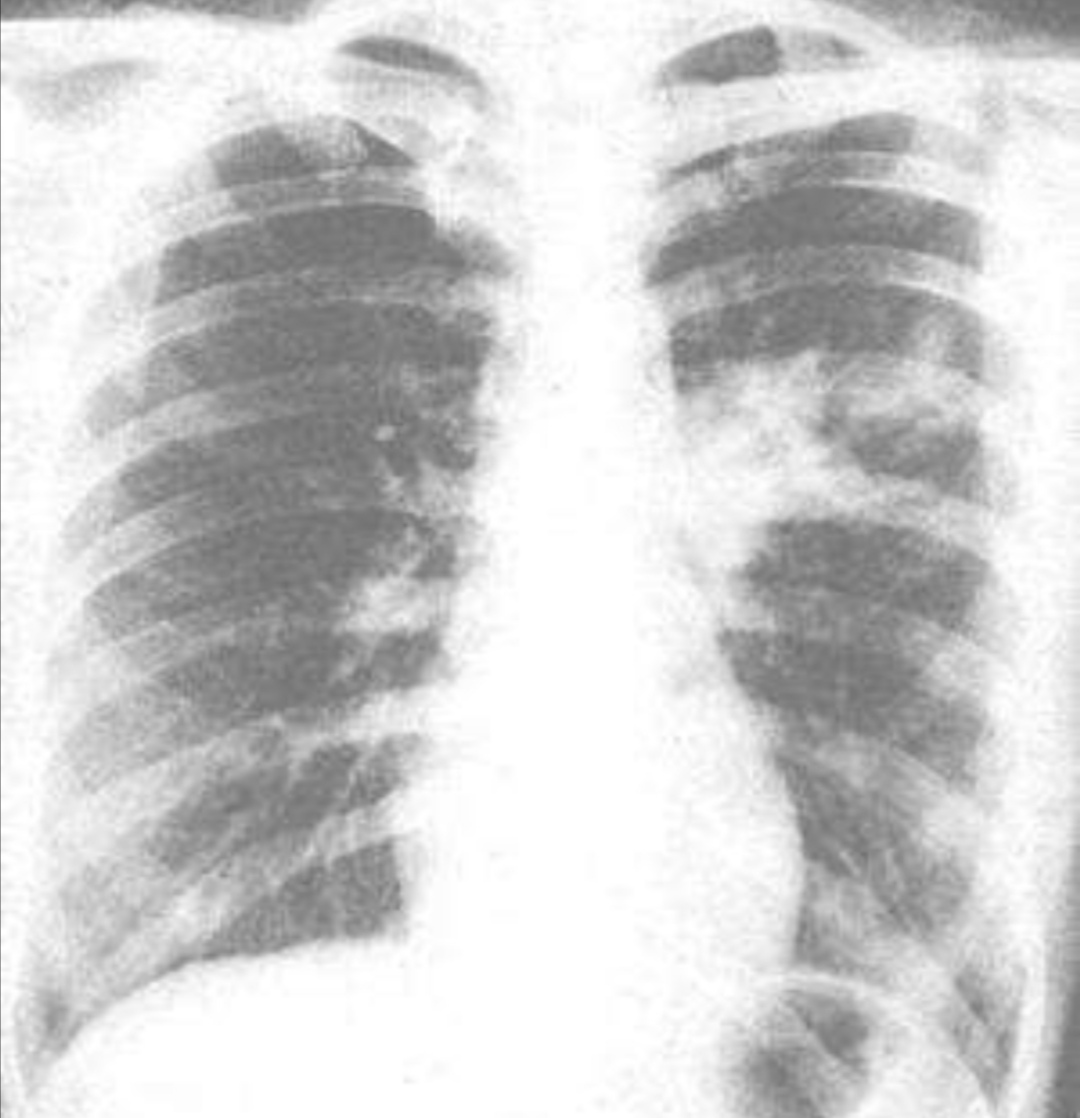

⑥肺部体征与症状以及影像学表现不一致是肺炎支原体肺炎的特征。